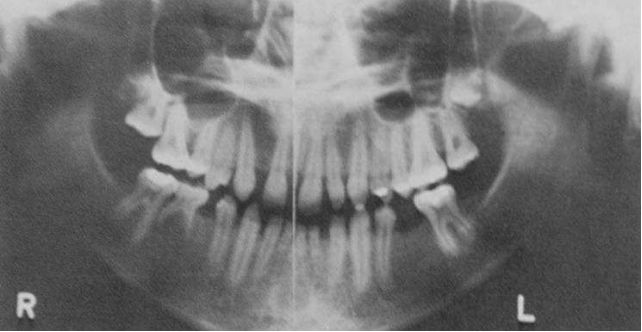

55.如全口環狀X光片所示,下顎骨左側可以發現多房性(multilocular) 放射線透光性病灶,並呈現有多顆牙齒之 牙根吸收,下列何者是較為可能之診斷? (A)鈣化齒源囊腫(calcified odontogenic cyst) (B) 含齒囊腫(dentigerous cyst) (C)齒源性角化囊腫(odontogenic keratocyst) (D)始基囊腫(primordial cyst)

66.15歲女孩丙下顎前方有一個無疼痛的腫脹而來求診,經X光檢査如附圖所示,病變區切片後,病理診斷為齒 源性角化囊腫,則此病患最可能罹患下列何種疾病? (A)艾迪森氏病(Addison's disease) (B)天使症(cherubism) (C)麥克滾-阿爾布萊德氏症候群(McCune-Albright syndrome) (D)痣樣基底細胞癌症候群(nevoid basal cell carcinoma syndrome)